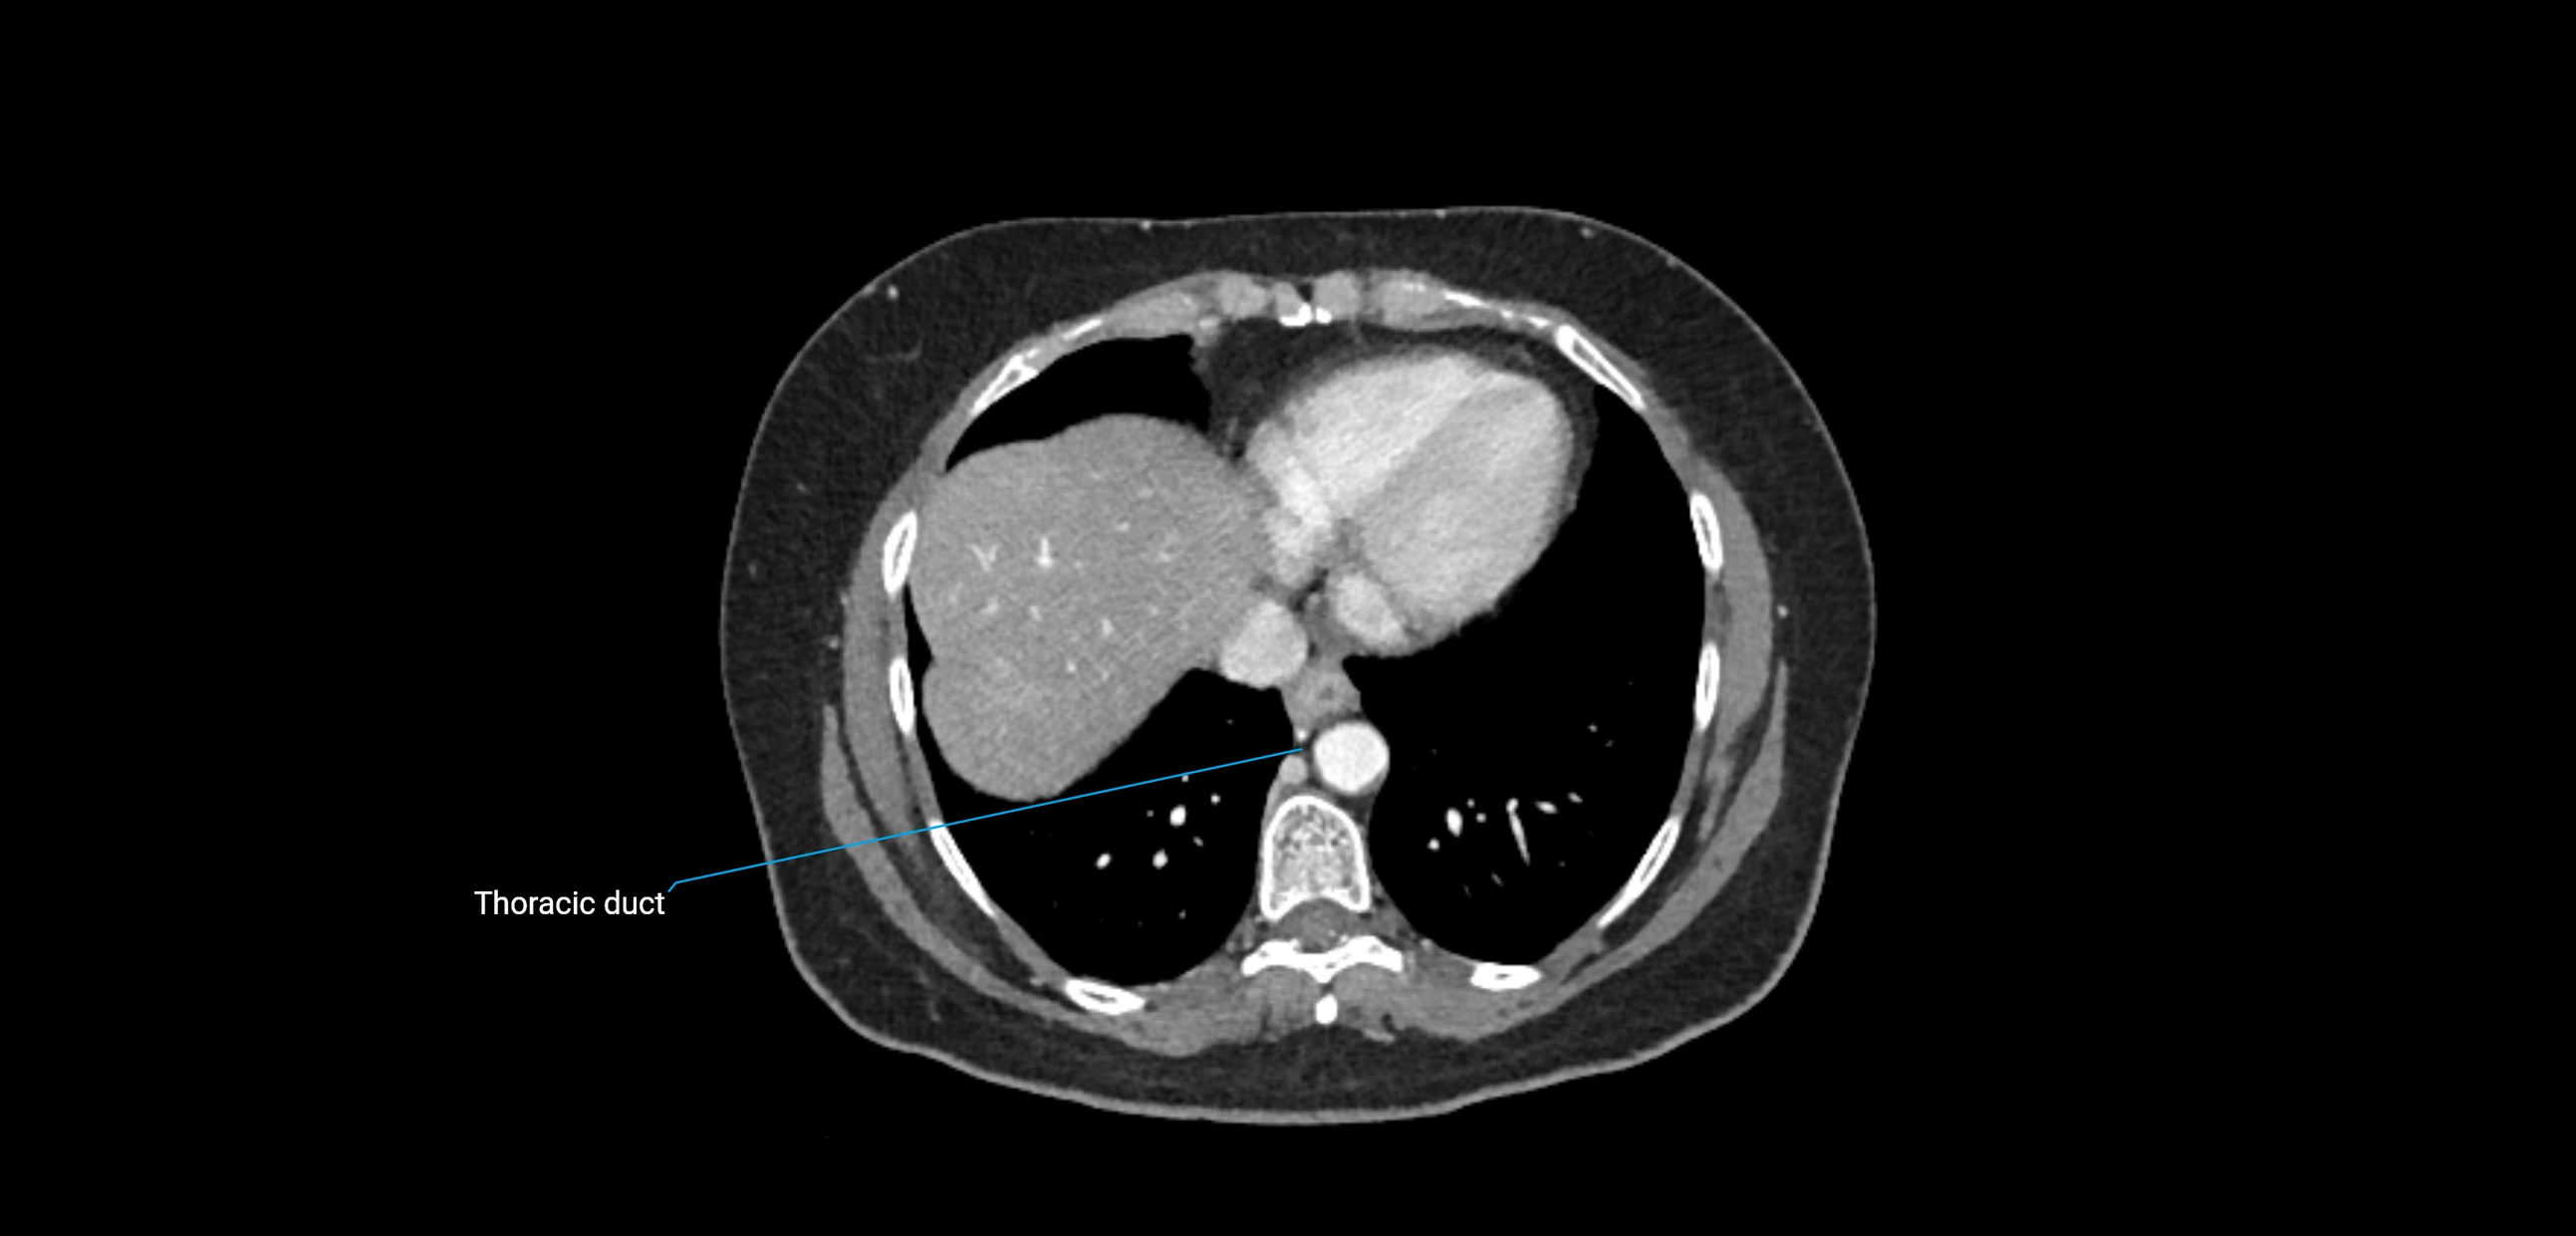

CT image

image